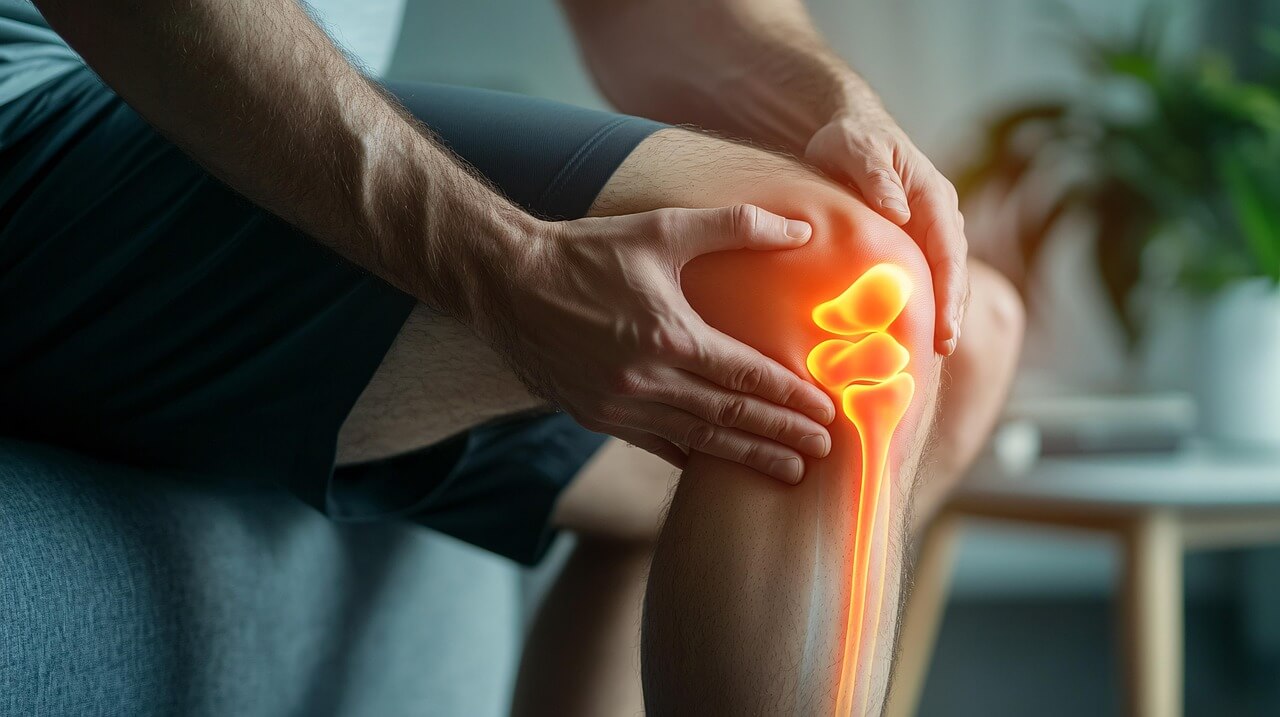

무릎은 우리 몸에서 가장 많이 사용되는 관절 중 하나로, 걷기, 앉기, 뛰기 등 모든 움직임에 필수적입니다. 따라서 무릎 통증의 원인은 단순 피로부터 연골 손상, 인대 파열, 퇴행성 관절염 등 다양한 질환으로 이어질 수 있습니다. 무릎 통증의 원인에 대한 놓치면 안되는 핵심가이드는 아래 버튼을 통해 확인하세요!

이 글에서는 무릎 통증의 원인을 세부적으로 살펴보고, 증상과 진단, 치료 및 예방 방법까지 정리하여 독자들이 자신의 상태를 이해하고 관리할 수 있도록 돕겠습니다.

무릎은 대퇴골, 경골, 슬개골이 이루는 복잡한 구조로, 인대와 연골, 반월상연골판 등이 관절 안정성을 담당합니다. 그러나 이 중 어느 하나라도 손상되면 무릎 통증의 원인이 됩니다.